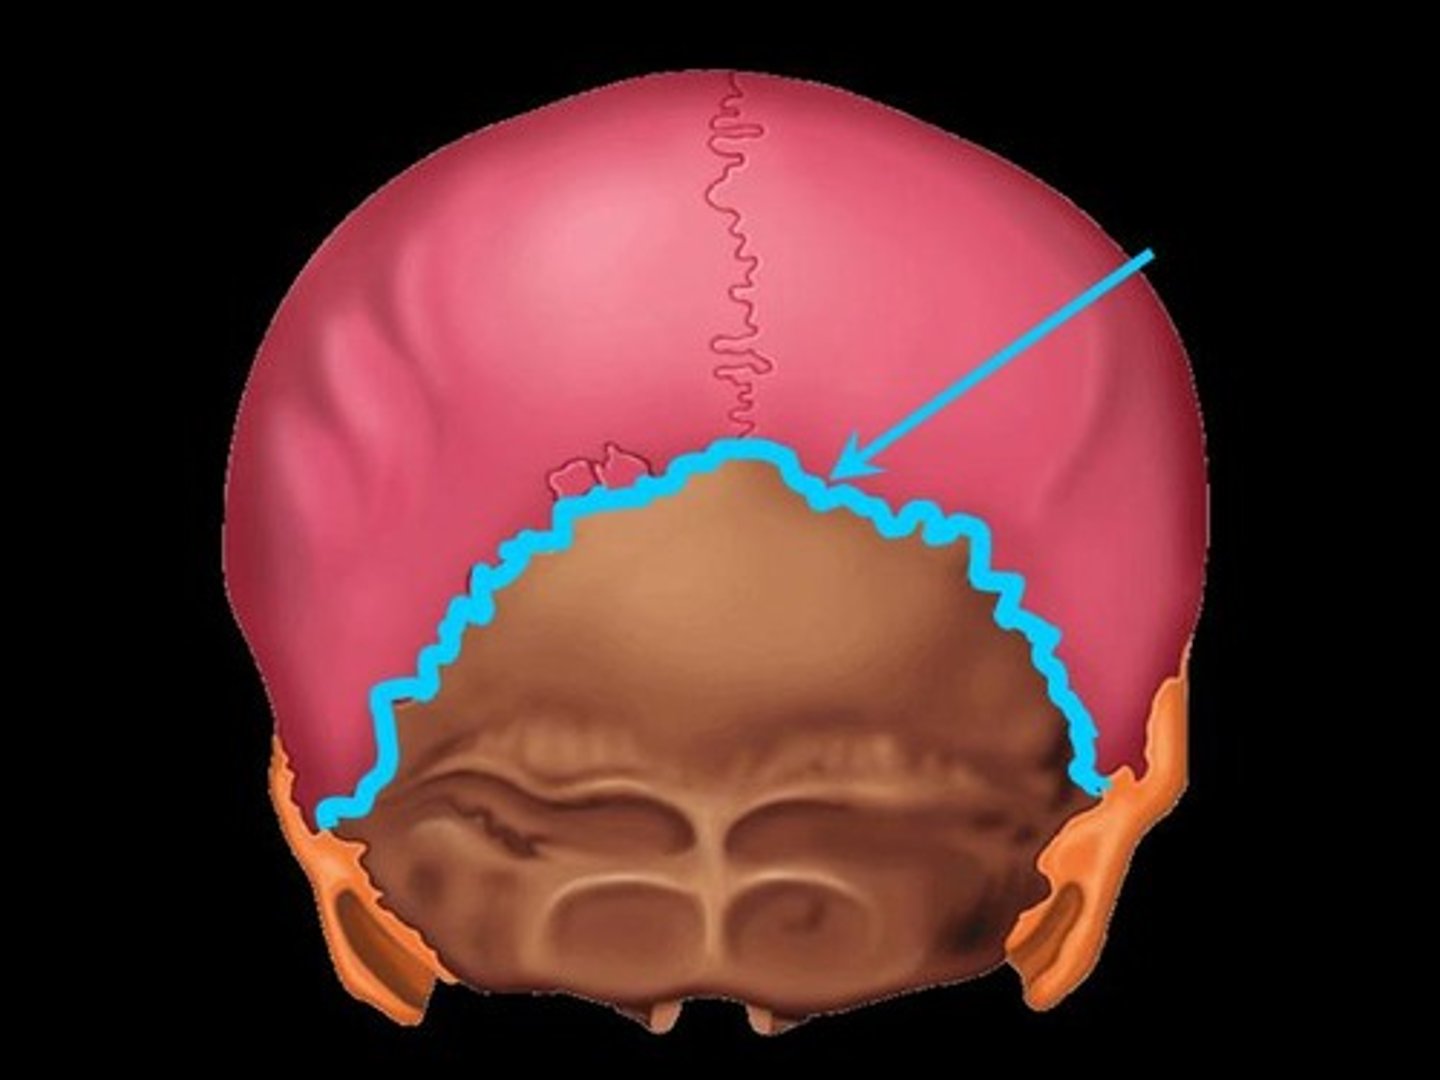

4 Main Sutures of the Skull

- Lamboid

Lamboid Suture

Suture between the occipital and parietal bones